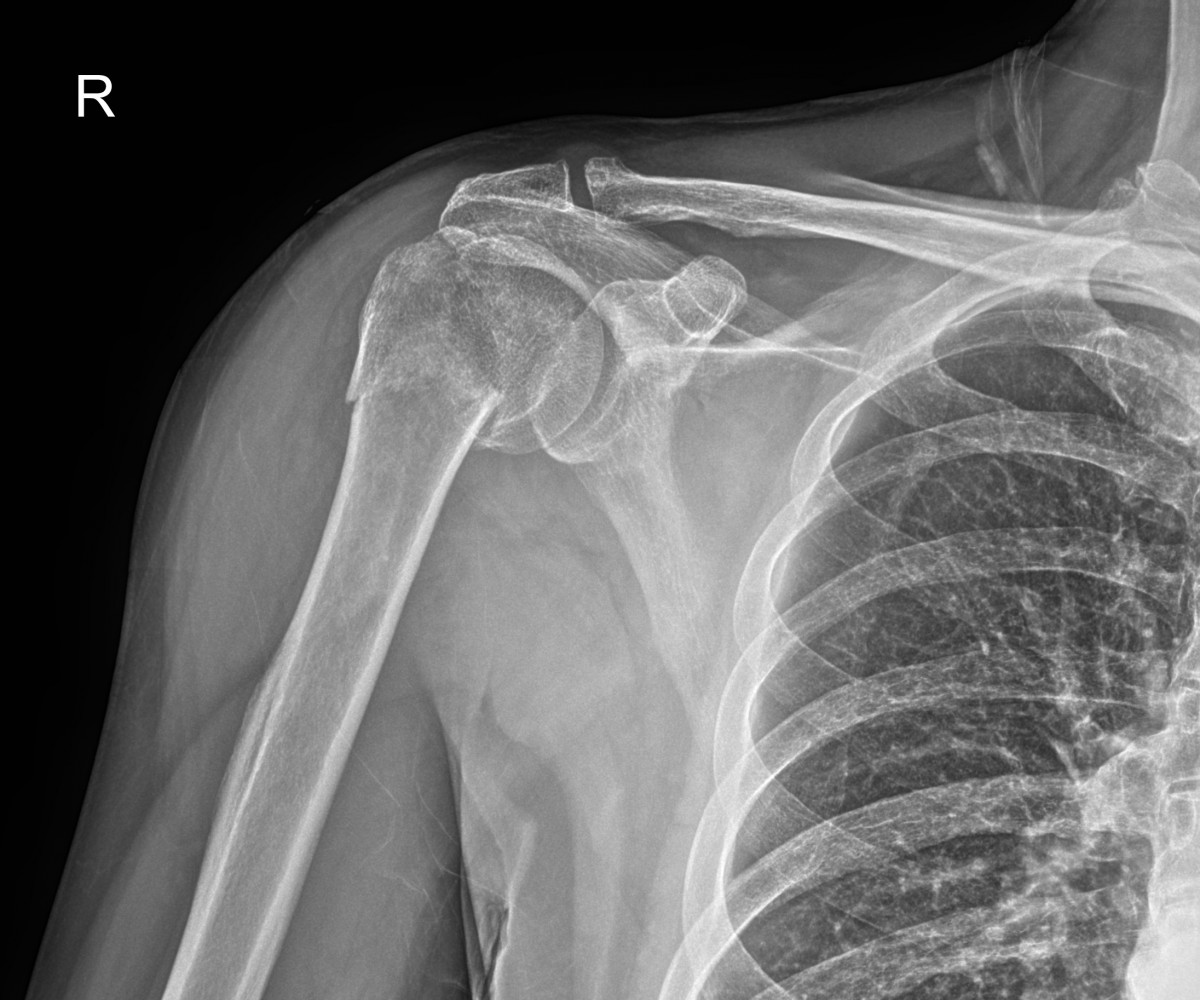

이재상원장님 어깨 골절 수술 박용O 환자

dae765e4d9ac96aee867c9d6292d8784_1758002699_4541.jpg